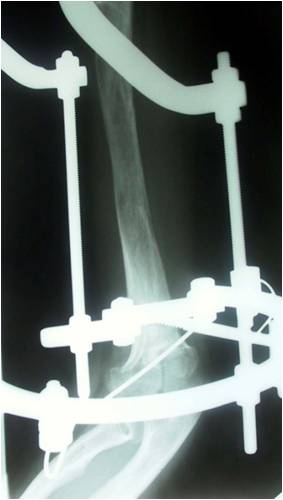

Blount disease is a developmental disorder characterized by disordered growth of the medial aspect of the proximal tibial physis resulting in progressive lower limb deformity. The deformity consists of varus, procurvatum, and internal rotation of the tibia, However, in the advanced stage of the disease, there is a bony bridge formation with medial plateau depression, joint instability, and leg length inequality, all of which have to be addressed by the proposed treatment. We treat this case by intra atticular osteotomy to elevation of medial plateau and another metaphyseal osteotomy to correct the varus and internal rotation deformities.

داء بلونت يطلق علي اعوجاج الساق المكون من هبوط باعلي الجزء الداخلي من اعلي عظمه الساق مع اعوجاج انسي بالساق و يتم علاج تلك الحالات بواسطه شقين عظميين احدهما خلال غظروف اعلي عظمه الساق والاخر بالجزء العلوي للساق مع الاستعدال التدريجي بواسطه مثبت خارجي مع العلم ان العلاج لا يرتبط بوزن المريض حيث يتم عمل العمليات بنجاح في الحالات السمنة الشديدة كما هو موضح بالصور